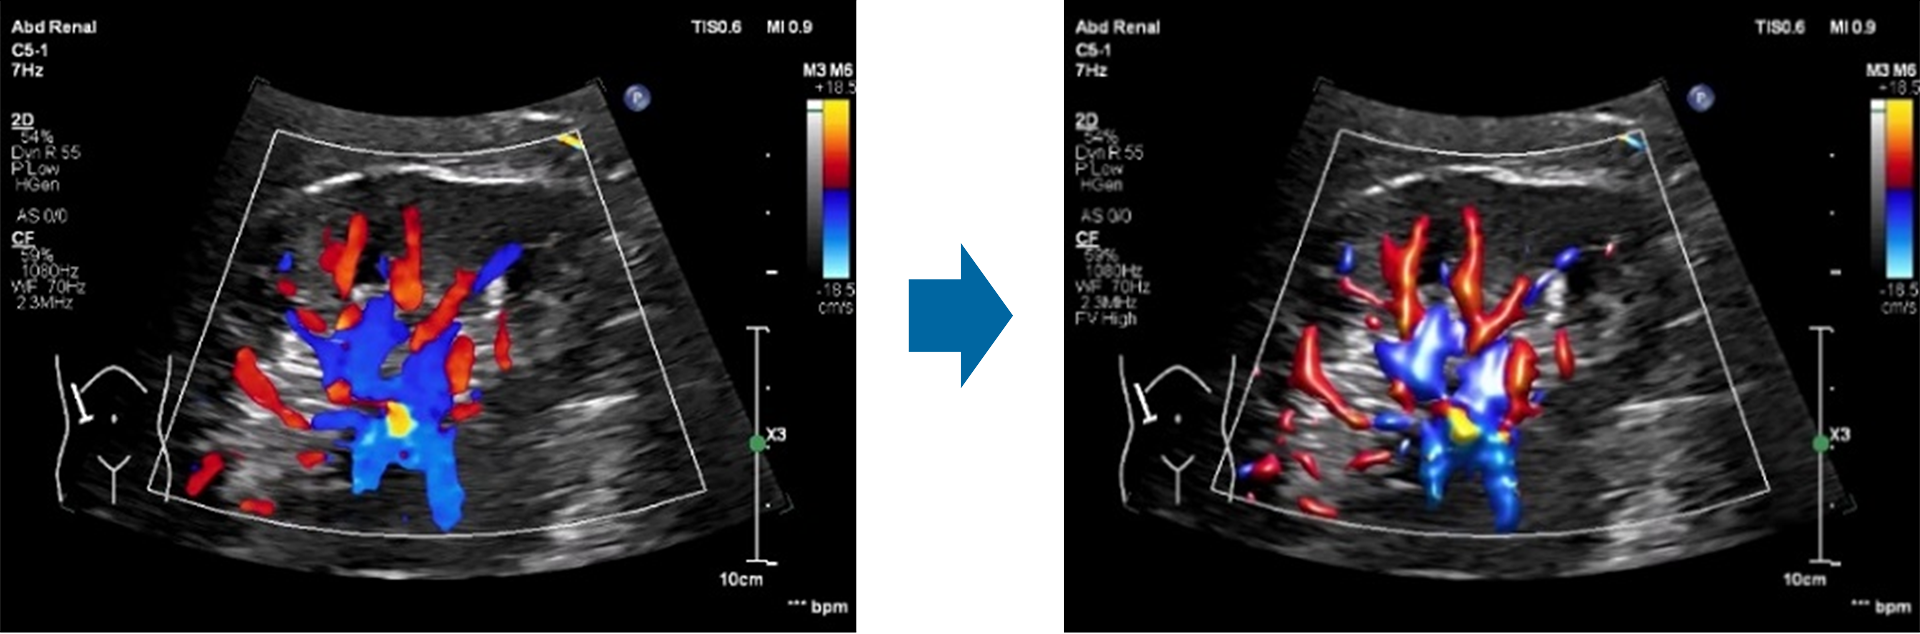

立体感のある血流イメージ「Flow Viewer」で視認性が格段に向上

「Flow Viewer」 は血流イメージに3 D のようなレンダリングを取り入れた表示法です。「Flow Viewer」はすべてのカラーモード(Color, CPA, Directional CPA, MFI, MFI HD)で使用可能で、血流に立体感を与えることで、従来のカラー画像に比べて、血管の鮮明度や境界の明瞭性に優れ、小血管の分岐と隣接血管の視認性が向上します。また、カラーの血管外へのはみだしや、呼吸などの動きによるにじみも減少し、これにより一目でより多くの臨床情報を把握することができます。

「Flow Viewer」による腎臓の血流イメージ:使用前(左)と使用後(右)システム間で共通するプラットフォーム